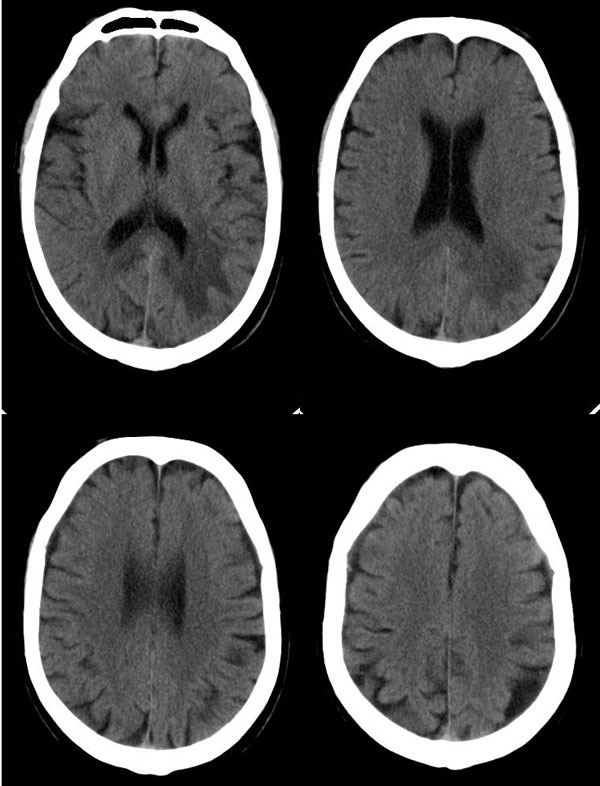

病灶平扫ct值约38hu,强化后明显强化,ct值约63hu,有一层ct值约72hu,病史:病人,男75,血压120/75,不高,头晕12天,平时体健,当时曾作胸x线片,正常。腹部ct,肝多发囊肿。经治疗(林格液+甘露醇)未用营养液及化疗药,当时诊断转移瘤。12天复查片如下

真的不可思议啊,难道是我们的确诊断错误,是颅内多发性出血灶?但为何前次会明显强化呢?

不对,还做过什么治疗?病人连做了2次ct扫描,是不是淋巴瘤受x线照射后病灶缩小、吸收的原因?不能大意,建议跟踪复查。

我还是坚持原来的意见,首先考虑淋巴瘤。

这么长时间了,怎么还没有结果?怎么误诊的?第二次ct见高密度灶消失,不过第一次有强化不应该是出血,还是考虑淋巴瘤。

病灶短期内经过治疗有明显变化。脑桥左侧部可见腔隙性脑梗塞,左枕叶病变考虑出血性脑梗塞可能性大。